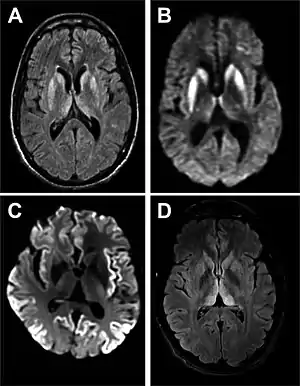

Imaging of the brain may be performed during medical evaluation, both to rule out other causes and to obtain supportive evidence for diagnosis. Imaging findings are variable in their appearance, and also variable in sensitivity and specificity.[43] While imaging plays a lesser role in diagnosis of CJD,[44] characteristic findings on brain MRI in some cases may precede onset of clinical manifestations.[45]

Brain MRI is the most useful imaging modality for changes related to CJD. Of the MRI sequences, diffuse-weighted imaging sequences are most sensitive.[46] Characteristic findings are as follows:

- Focal or diffuse diffusion-restriction involving the cerebral cortex and/or basal ganglia. In about 24% of cases DWI shows only cortical hyperintensity; in 68%, cortical and subcortical abnormalities; and in 5%, only subcortical anomalies.[47] The most iconic and striking cortical abnormality has been called "cortical ribboning" or "cortical ribbon sign" due to hyperintensities resembling ribbons appearing in the cortex on MRI.[48] The involvement of the thalamus can be found in sCJD, is even stronger and constant in vCJD.[49]

- Varying degree of symmetric T2 hyperintense signal changes in the basal ganglia (i.e., caudate and putamen), and to a lesser extent globus pallidus and occipital cortex.[44]

| Signal hyperintensity in the caudate nucleus and putamen on diffusion-weighted and FLAIR MRI | Often present | Often absent |

| Pulvinar sign-bilateral high signal intensities on axial FLAIR MRI. Also posterior thalamic involvement on sagittal T2 sequences | Not reported | Present in >75% of cases |